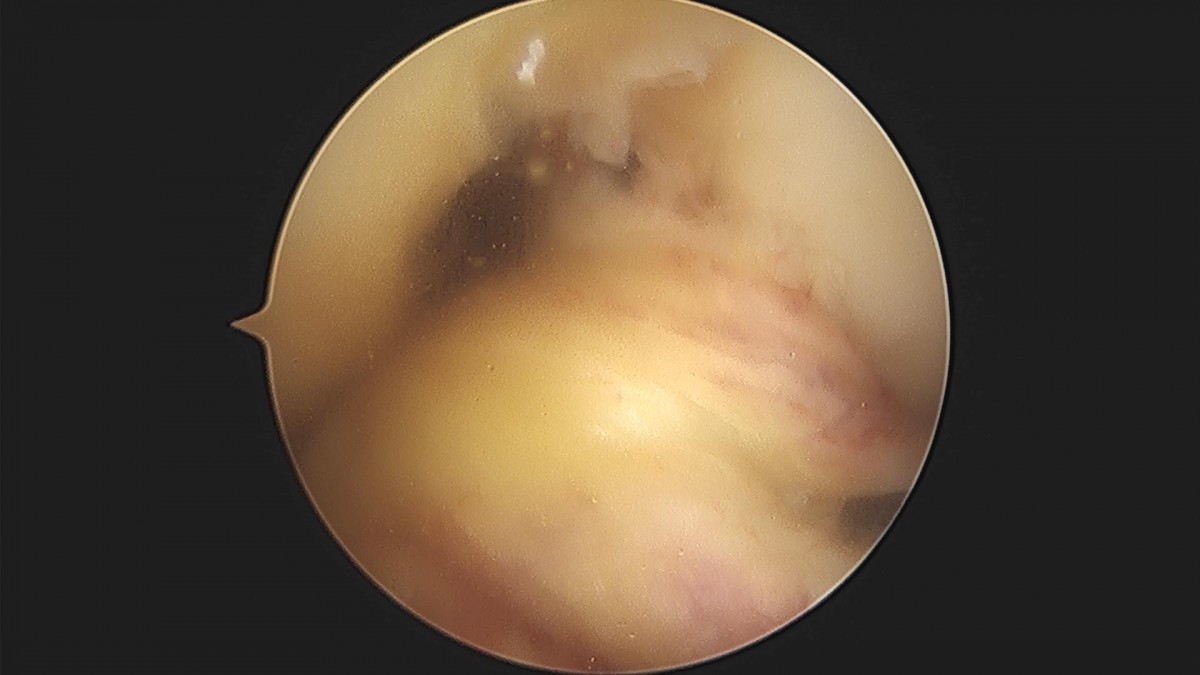

배우한원장님 무릎 전방십자인대 재건술 김인O 환자

9bd32f36aa7dff884b615e35b18923ca_1657593785_3223.jpg

9bd32f36aa7dff884b615e35b18923ca_1657593785_9886.jpg

9bd32f36aa7dff884b615e35b18923ca_1657593786_6401.jpg

9bd32f36aa7dff884b615e35b18923ca_1657593787_314.jpg

9bd32f36aa7dff884b615e35b18923ca_1657593787_9716.jpg

9bd32f36aa7dff884b615e35b18923ca_1657593788_6723.jpg

9bd32f36aa7dff884b615e35b18923ca_1657593789_3743.jpg

9bd32f36aa7dff884b615e35b18923ca_1657593790_0696.jpg

9bd32f36aa7dff884b615e35b18923ca_1657593790_7493.jpg

9bd32f36aa7dff884b615e35b18923ca_1657593791_4475.jpg